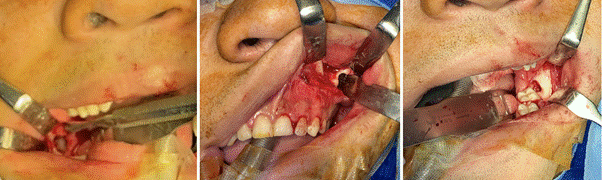

Under general anesthesia and orotracheal intubation, the following procedures were performed: enucleation of the mandibular lesions, peripheral curettage/osteotomy followed by MCS application for 3 minutes, and placement of a decompressive cannula in the left maxillary lesion. The cannula was kept patent, with daily rinses using 0.12% chlorhexidine until adequate decompression was achieved to allow subsequent enucleation (Figure 3). The patient is currently under monthly clinical follow-up and radiological monitoring every 6 months.